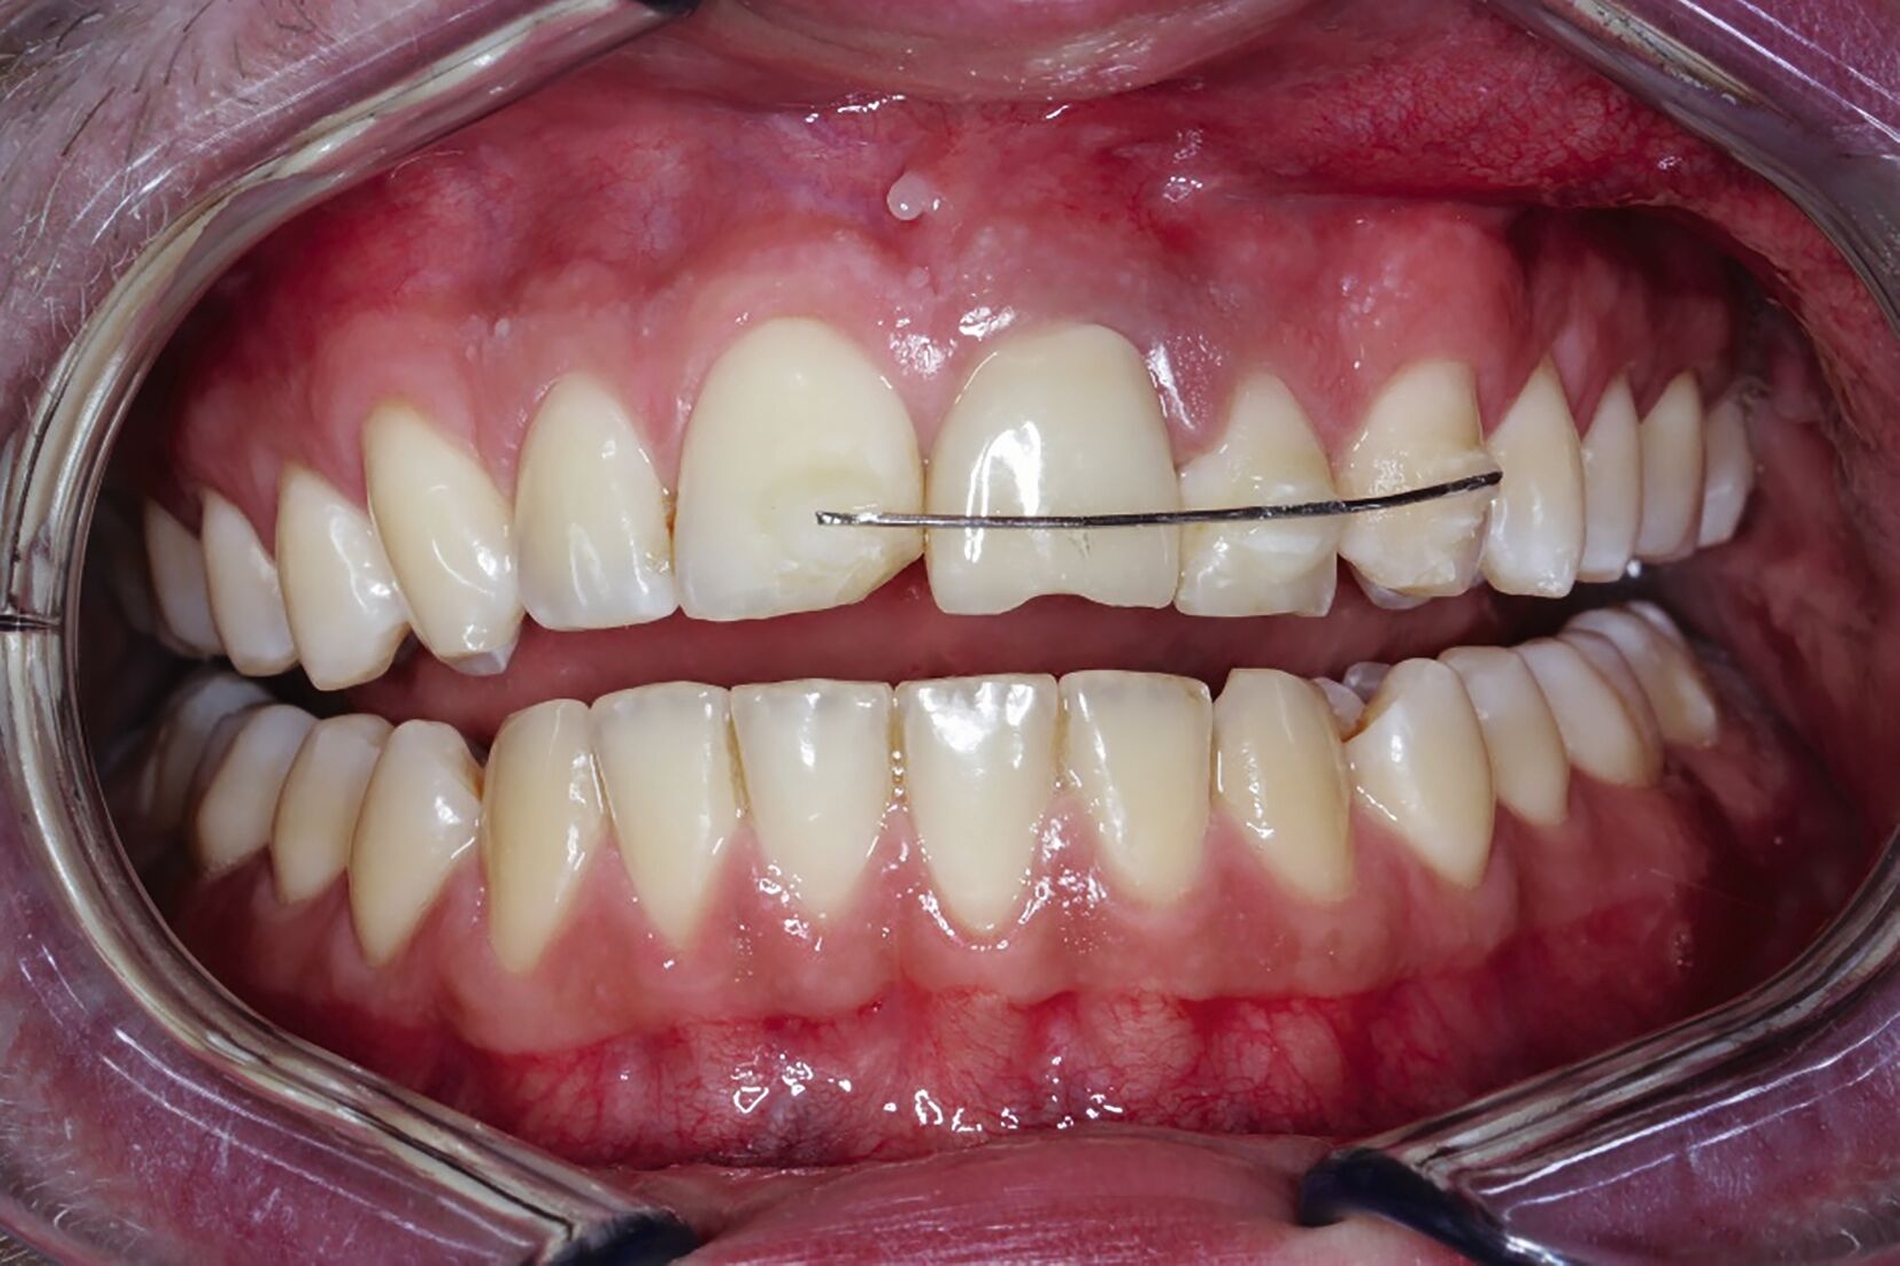

Nachfolgend konnte die Multibracket-Apparatur (MBA) für die Extrusion in Segmentbogentechnik befestigt werden (Abbildung 10). Dazu wurden die zu beklebenden Kompositflächen mit Aluminiumoxid-Pulver gestrahlt und mit einem Silan-haltigen Haftvermittler benetzt. Anschließend wurde drei Monate die kieferorthopädische Extrusionstherapie durchgeführt (Abbildungen 10 bis 12). Der Patient stellte sich wöchentlich zur Fibrotomie vor, um eine Verlagerung der Gingiva nach koronal zu vermeiden. Aufgrund der nach koronal gerichteten Bewegung erfolgte im Bedarfsfall das Einkürzen der Schneidekante.